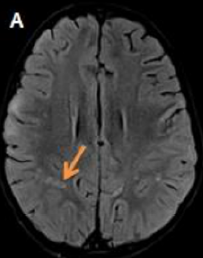

Case Report

Acute Disseminated Encephalomyelitis

Nourrelhouda Bahlouli, Fatima Chait, Nazik Allali, Siham El Haddad and Latifa Chat. 12(6): 73-75.